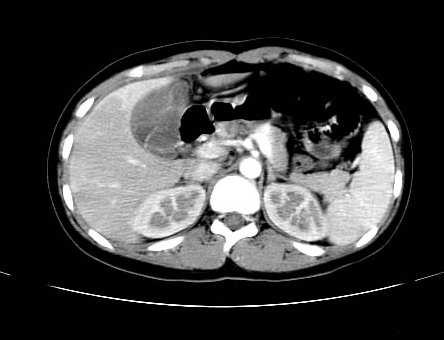

女 16岁  右上腹痛一天,无其他不适

肿块最大径位于十二指肠降段与水平段移行处,并且与肝脏压迹呈“0”形征,可以考虑位于肝外并与胃肠道关系紧密,考虑胃肠道间质瘤(gist)可能较大,须除外神经节起源肿瘤。

肿块与十二指肠关系密切,支持间质瘤诊断.肝脏与结肠均为受压改变.

右下腹巨大肿快,密度不均匀,内见坏死低密度区,边界清楚,与周边胀器明显有分界,未见强化,多考虑来源于间叶组织的良性肿物.

病灶巨大,少部分向肠腔内生长,大部分向长腔外生长。其密度不均匀,增强显示明显不均匀强化,并见有大片状始终不强化的不规则坏死液化区。虽然病灶中上部形态尚可,病人又如此年轻,但中下部形态、密度、强化特点强烈提示为恶性病灶。综上,我考虑本病例为:恶性胃肠道间质瘤。